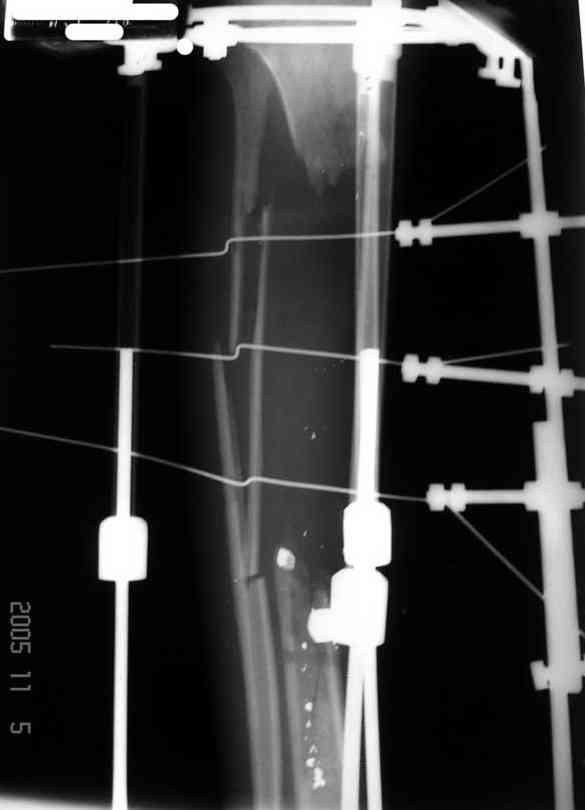

3,4 - через 4 недели наложен спице-стержневой аппарат, произведена остеотомия большеберцовой кости в верхней трети, раны зажили, проводилась дистракция в аппарате.

5, 6 - через 2,5 мес после травмы выполнен закрытый остеосинтез блокируемым штифтом.